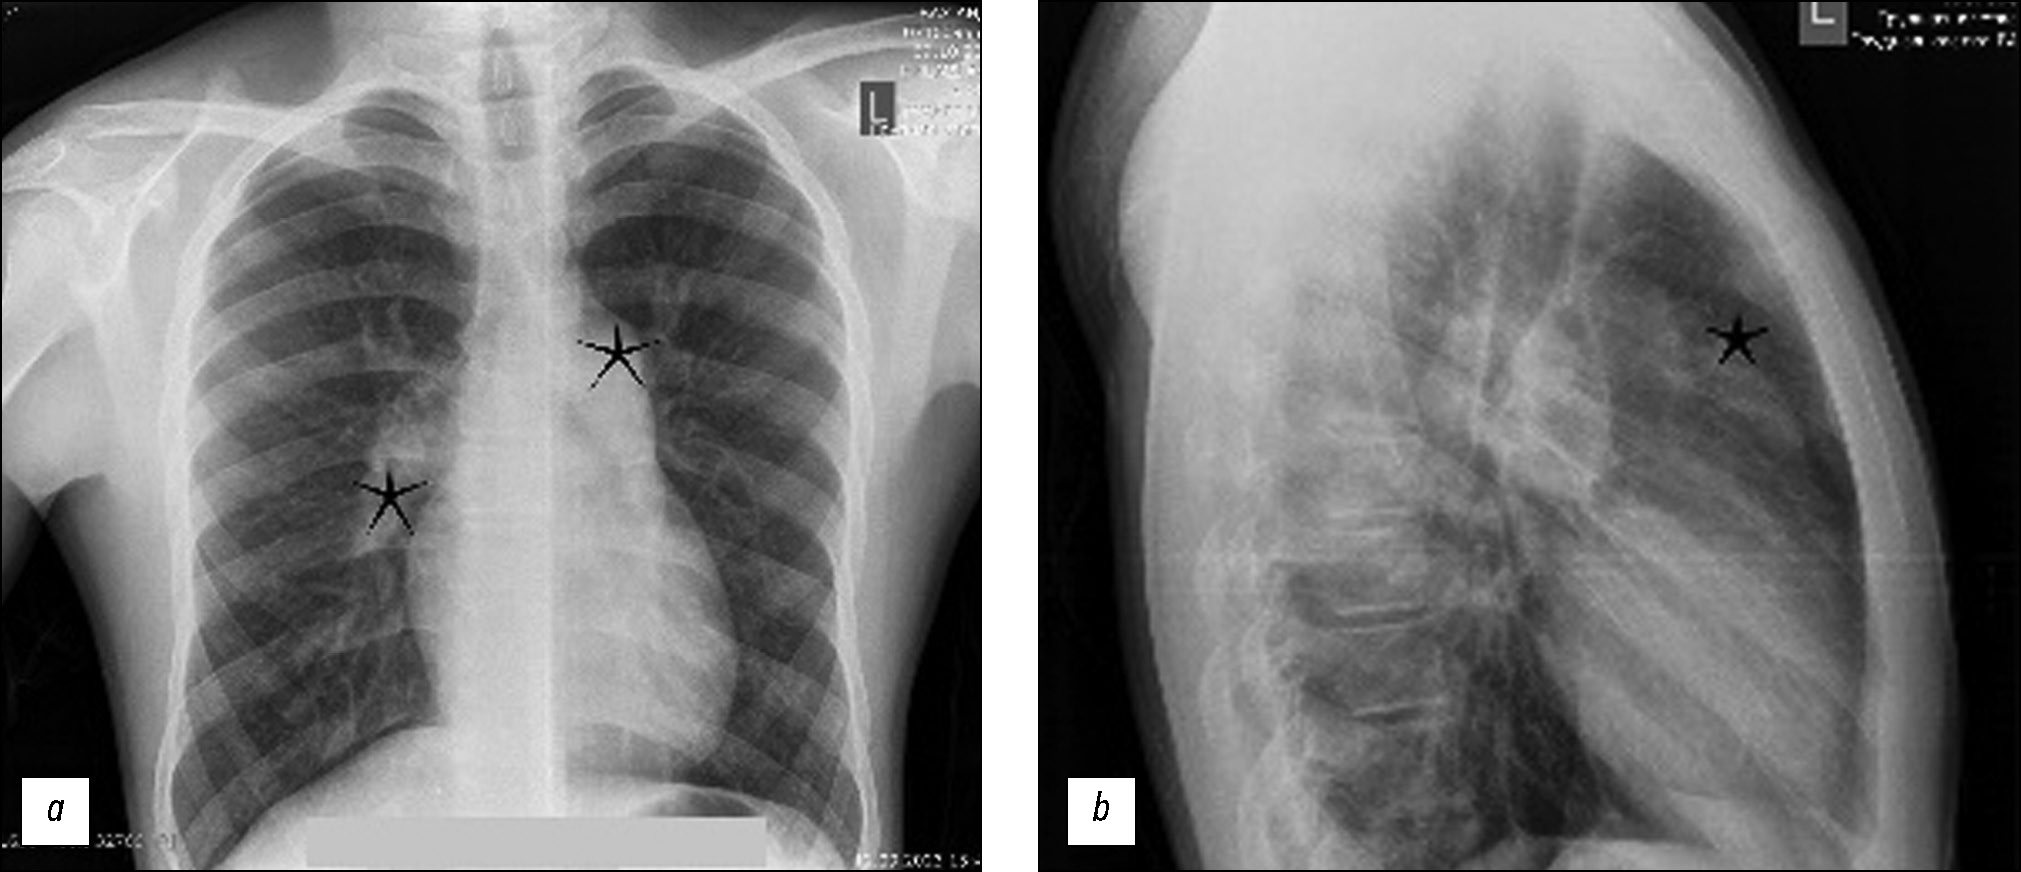

На рентгенограммах органов грудной клетки выявлено расширение центральных лёгочных артерий и правого желудочка, что свидетельствует о лёгочной гипертензии (рис. 1). На фибробронхоскопии выявили тромб в просвете VΙ сегментарного бронха и кровотечение алого цвета. Поскольку у пациента были повторные эпизоды кровотечения, наблюдалось снижение уровня гемоглобина.

Рис. 1. Рентгенограммы органов грудной клетки, демонстрирующие расширение центральных лёгочных артерий и правого желудочка, что свидетельствует о лёгочной гипертензии: a — заднепередняя проекция, на снимке отмечается расширение лёгочных артерий (обозначено чёрными звёздочками); b — боковая проекция, на снимке отмечается увеличение правого желудочка (обозначено чёрной звёздочкой).